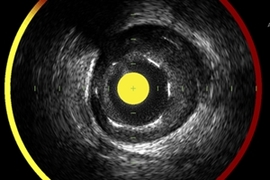

Infrared spectroscopy to tackle blocked coronary arteries

Hybrid ultrasonic-photonic mapping catheter system is now available in Japanese hospitals.